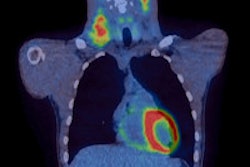

Through its IsoRay Medical subsidiary, IsoRay is the sole producer of cesium-131 brachytherapy seeds, according to the firm.